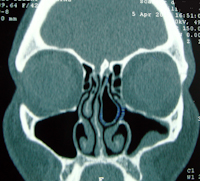

TRAITEMENT D'UNE SINUSITE ASSOCIEE

Il peuvent coexister aux troubles ventilatoires notamment une sinusite chronique ou une tendance aux sinusites aiguës répétées, elle peuvent alors être traitée dans le même temps par une méatotomie c'est-à-dire un agrandissement de l'orifice naturel du sinus maxillaire dans la fosse nasale. Seuls les sinusites majeurs où les polyposes nasales justifient une intervention chirurgicale en deux temps.

Pour toutes ces interventions il s'agit de microchirurgie endoscopique sans cicatrice et sans oedème extérieur ajouté.  Le scanner pré-opératoire est un élément radiologique indispensable avant ce type d'intervention.

Sinusite maxillaire gauche   corps étranger  du méat sinusien droit